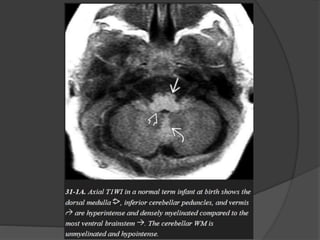

INFRATENTORIAL

 Dorsal medulla /

midbrain

 Inferior / superior

cerebellar peduncles

 Middle cerebellar

peduncle

 Cerebellar white

matter

T1WI T2WI

First appear at

Birth Birth

1 mth 3 mth

1 – 3 mth 8 – 18 mth

 Dorsal medulla / mid brain.

 Inferior / superior cerebellar peduncles.

 Posterior limb of internal capsule.

 Ventrolateral thalamus.

One month

 Deep cerebellar white matter.

 Corticospinal tract.

 Pre / post central gyri.

 Optic nerve / tracts.

Three month

 Cerebellar folia.

 Ventral brainstem.

 Optic radiation.

 Anterior limb of internal capsule.

 Occipital subcortical U fibers.

 Corpus callosum splenium.

Six month

 Corpus callosum genu.

 Paracentral subcortical U fibers.

 Centrum semioval ( Partial ).

Eight month

 Centrum semiovale ( complete except

frontoteporal area ).

 Subcortical U fibers ( complete except most

rostral frontal area ).

Eighteen month

 Essentially like adult.

Myelination milestones after

birth

T1WI

 3 m cerebellar white

 4 m corpus callosum

splenium

 6 m corpus callosum

genu

T2WI

 8 m corpus callosum

 11 m anterior limb

internal capsule

 14 m frontal white